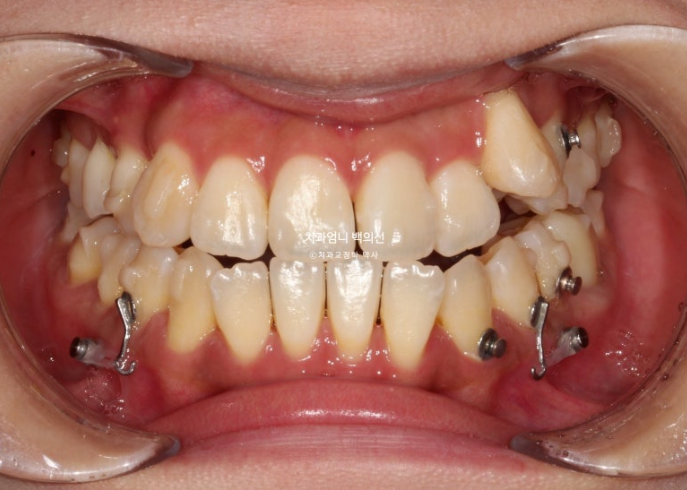

23년 9월부터 24년 5월까지, 8개월간 장치를 낀 모습입니다.

치료시작

24.05

8개월간 앞니에선 큰 변화가 없죠?

어금니를 하나씩 뒤로 보내느라 초반 8개월을 대부분 소모합니다. 교정용 나사인 미니스크류도 각 분악당 최소 1개씩은 필요합니다.

다행히 환자분은 장치를 성실하게 껴주었습니다.